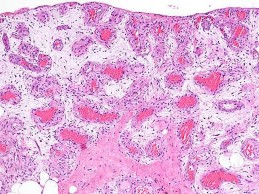

A 35-year-old female is diagnosed with a locally aggressive giant cell tumor of the distal radius. Preoperative administration of Denosumab is planned to facilitate downstaging and joint-salvage surgery. What is the exact mechanism of action of Denosumab in this context?

Explanation

Denosumab is a fully human monoclonal antibody that specifically binds to RANKL (Receptor Activator of Nuclear factor Kappa-B Ligand). By binding to RANKL, it prevents it from interacting with the RANK receptor on the surface of osteoclasts and osteoclast precursors. In Giant Cell Tumor of bone, the neoplastic mononuclear stromal cells express high levels of RANKL, which aggressively recruits and activates the reactive multinucleated giant cells (osteoclasts) that cause bone destruction.